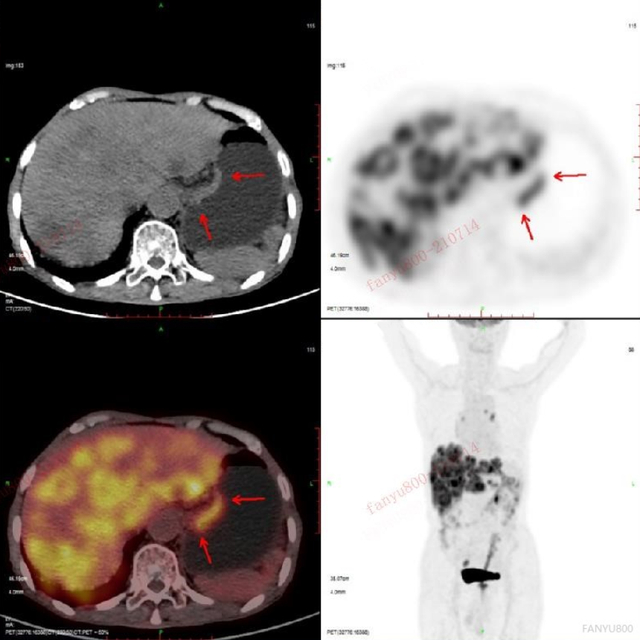

男性,78岁

相关病史:一直觉得腹部疼痛,在基层医院CT检查,发现肝脏多发低密度灶,怀疑为肝脏多发转移。之后患者在平安健康(检测)中心接受PET/CT检查。

PET/CT影像学表现

上图为肝脏的横断位、冠状位及矢状位图像,依次为PET图像、CT图像、融合图像。图示肝脏体积稍增大,肝内弥漫分布大小不等类圆形低密度灶,部分相互融合,边界不清 ,相应部位放射性摄取明显增高,SUV最大值8.50。

上图显示横断位示胃充盈佳,胃体小弯侧增厚,相应部位放射性摄取异常增高,SUV最大值6.29。

上图中冠矢状位也清楚地显示胃体小弯侧的增厚及FDG代谢的增高。

PET/CT找出原发灶

最后PET/CT诊断为胃癌伴肝脏多发转移,给临床指明了方向,可以制定更针对性的治疗方案。